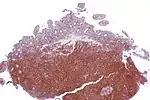

![]() | |

| Micrograph showing mantle cell lymphoma (bottom of image) in a biopsy of the terminal ileum. H&E stain. | |